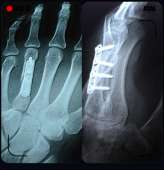

20171001220423.png (1144Кб, 1440x1439)

Screenshot20171[...].jpg (718Кб, 1254x1298)

Такие дела. Прошел пятый год, только сейчас опомнился, надо железку доставать, рука иногда болит, здороваться с крепкими парнямия больно.

Хирург сказал нихуя, перелом с осколками, хуево срастется без него, хотя смотрю на рентген, как-то один хуй криво кость срослась.